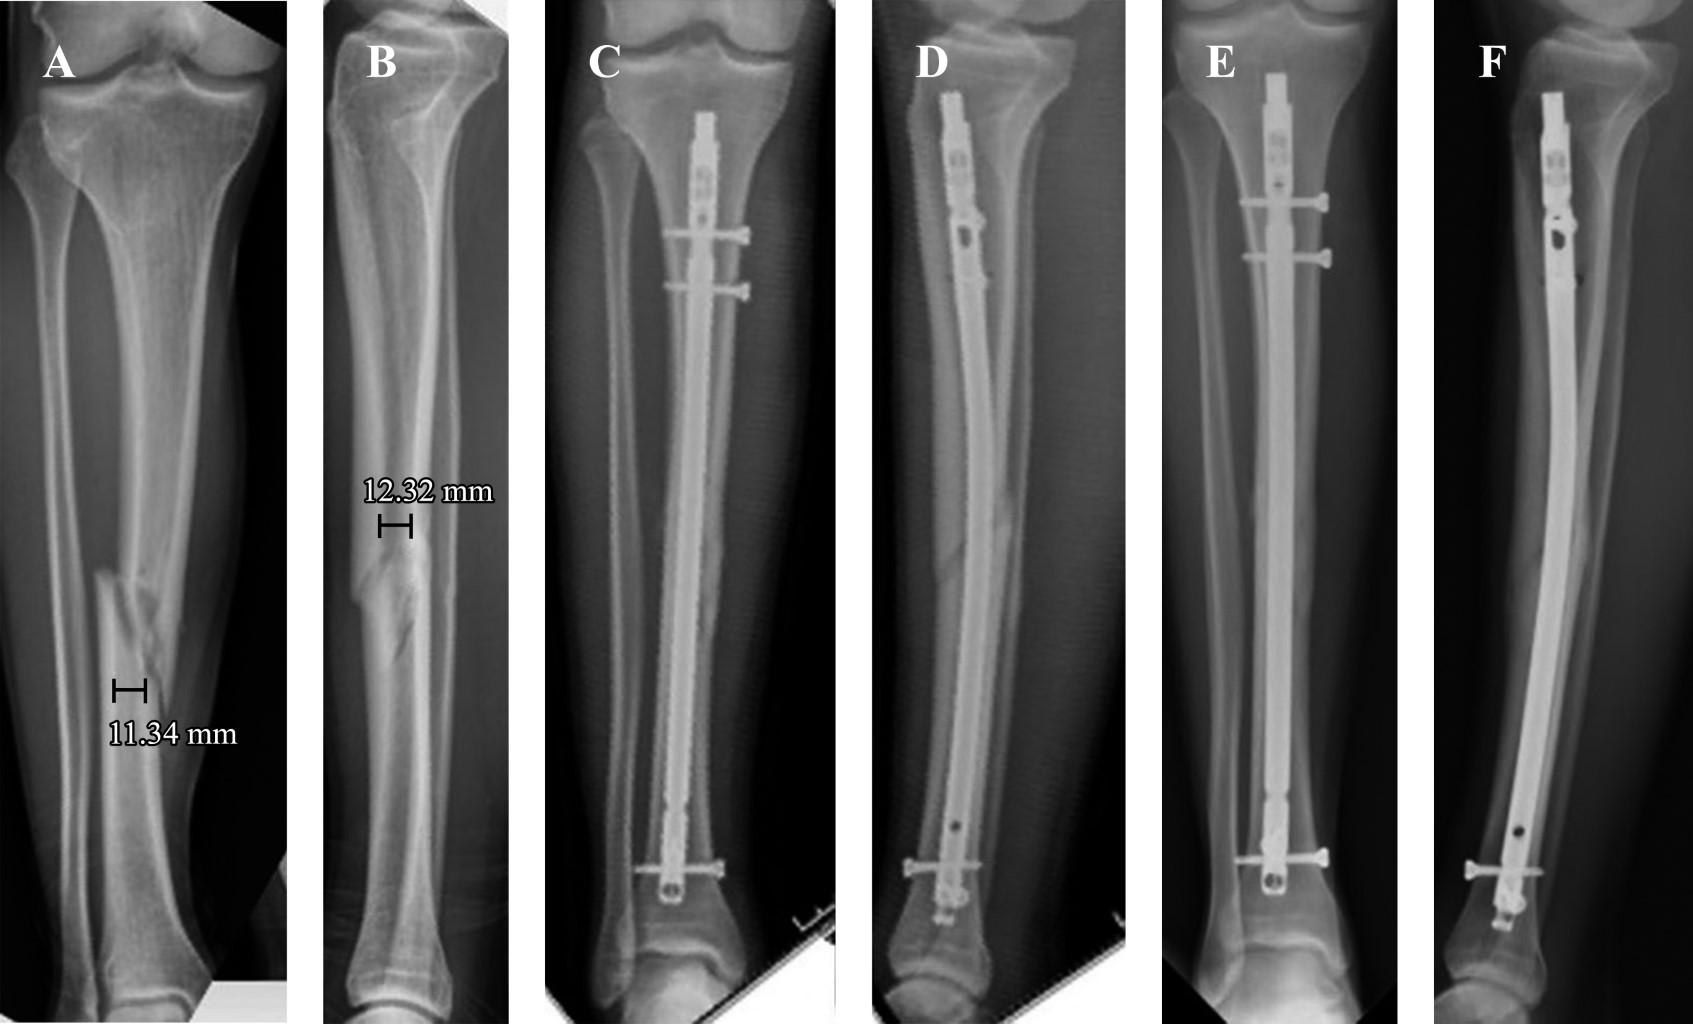

El análisis radiográfico fue realizado utilizando las proyecciones anteroposterior (AP) y lateral (L) de pierna. Con las radiografías del ingreso catalogamos las fracturas según la clasificación OTA/AO. Para determinar el diámetro del canal medular y evitar un sesgo de precisión utilizamos el software digital Synapse (Fujifilm Corporation) de nuestro centro. Dichas mediciones se realizaron en ambas proyecciones radiográficas (AP y L) a nivel del istmo en las radiografías de la lesión (Figura 1). Estas mediciones se realizaron en dos oportunidades (con un intervalo de tres meses) por dos observadores independientes y las diferencias se resolvieron por consenso junto al cirujano más experimentado. El diámetro del clavo se obtuvo de los registros del protocolo quirúrgico.

La tasa de consolidación fue de 91.7% (n = 88), en una media de tiempo de 5.1 ± 2.3 meses posterior a la cirugía (Figura 2). Ocho (8.3%) pacientes evolucionaron con falla, de los cuales tres (3.1%) presentaron retardo de consolidación, logrando la curación ósea con la dinamización del clavo realizada a las 12, 14 y 20 semanas en cada caso. Los cinco (5.2%) restantes desarrollaron seudoartrosis y fueron tratados mediante un recambio del CEM por uno de mayor diámetro y, además, en dos de ellos se utilizó aloinjerto óseo.

Figura 1